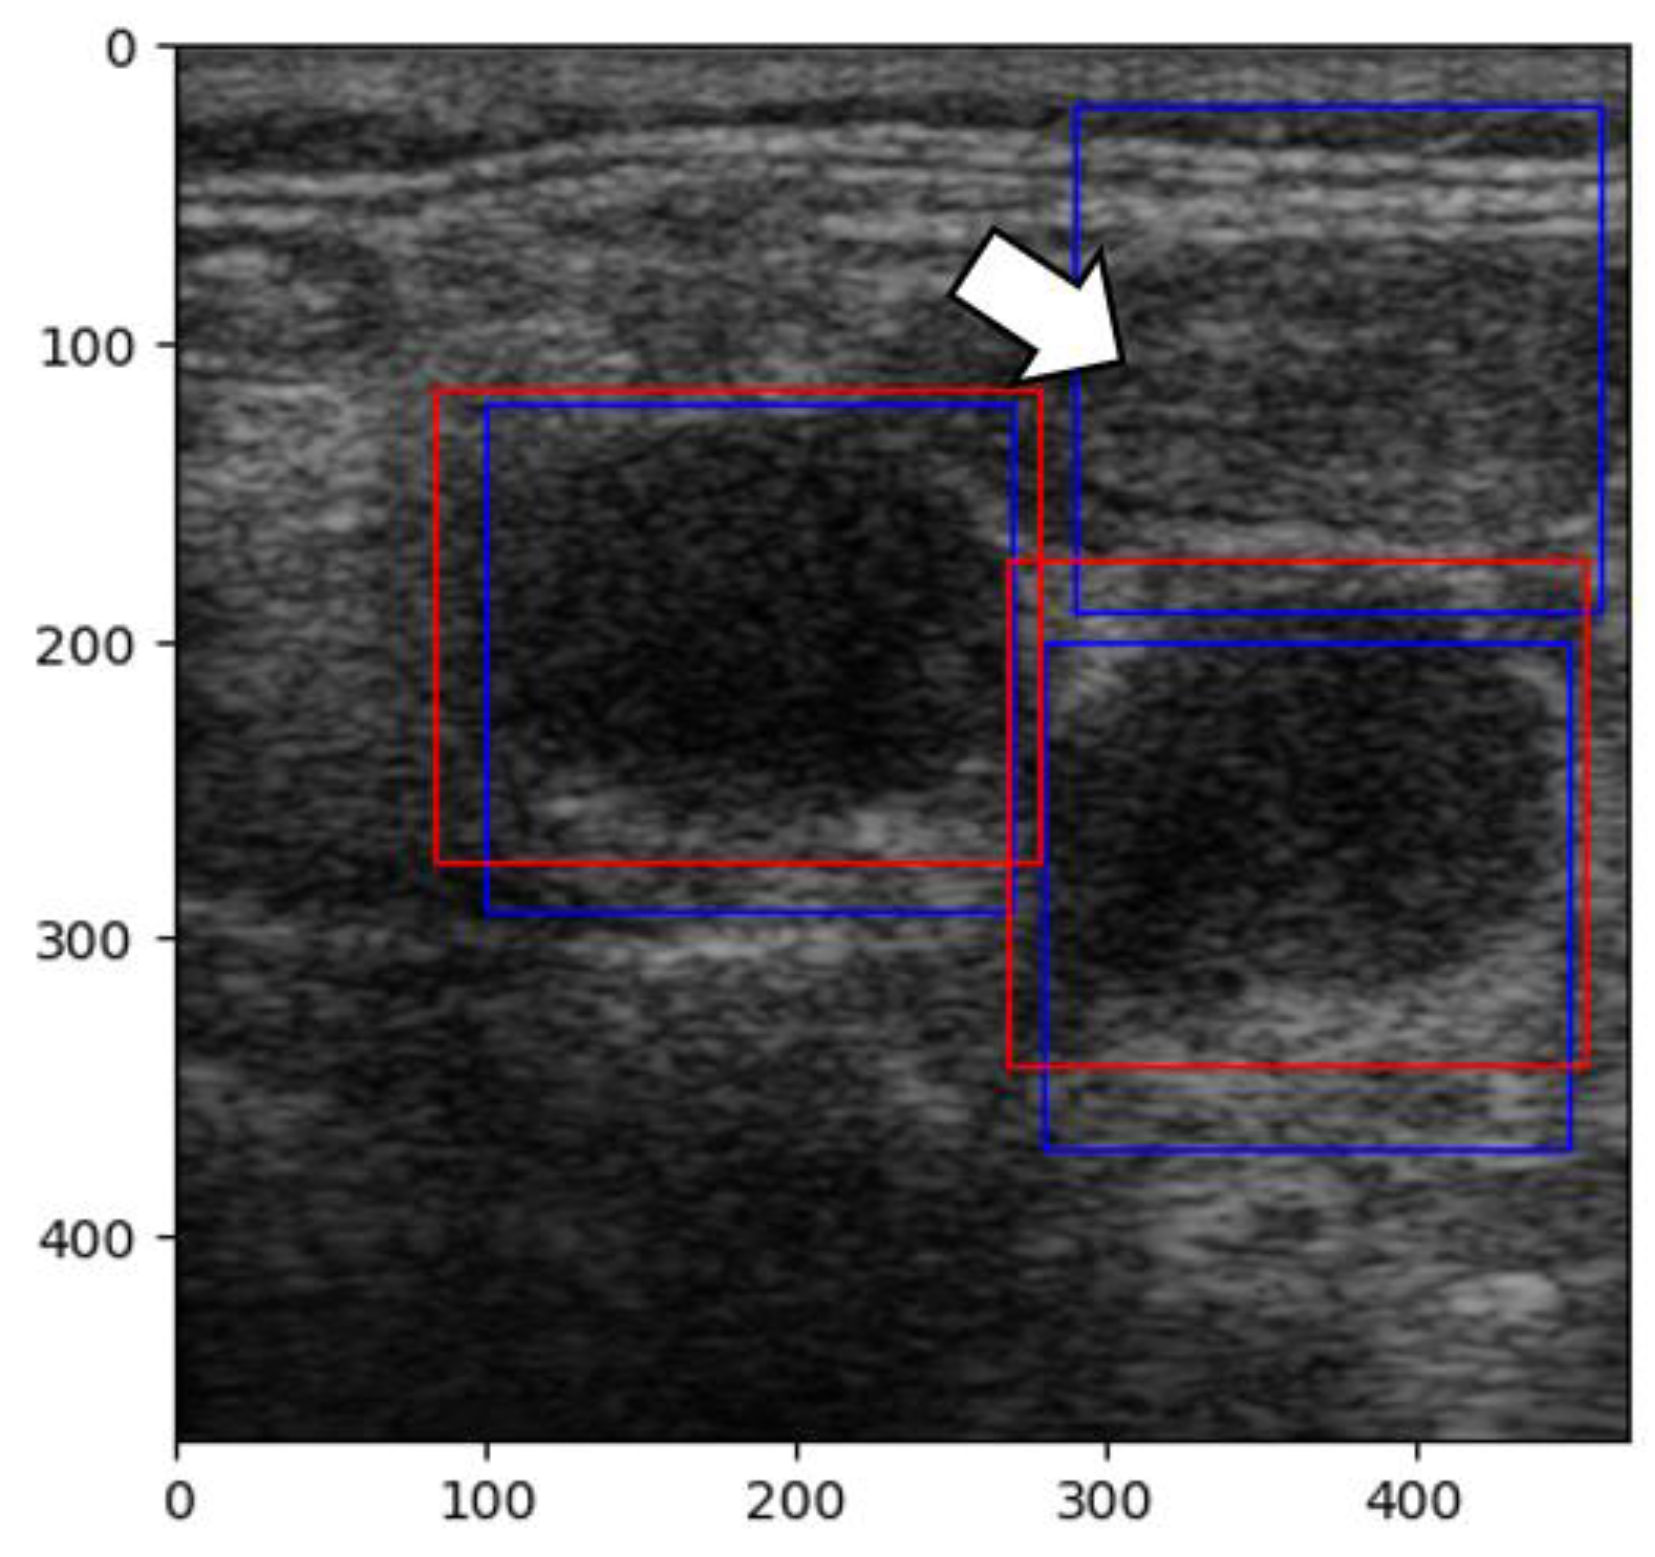

In our second attempt, we rebuilt the CNN using the sliding window technique. The sliding window technique involves moving a fixed or variable-size window through a data structure (an image, in our case) to efficiently solve problems involving continuous subsets of elements. This method efficiently identifies specific criteria present in data [35]. The images were pre-processed by normalizing the pixels’ values between 0 and 1. With this new technique, new challenges arose because of prediction overlap, which prevented us from correctly calculating the IoU between labels and predictions (Figure 11).

Figure 11. Desaturated image with overlapping labels. Red squares: labels. Blue squares: predictions.